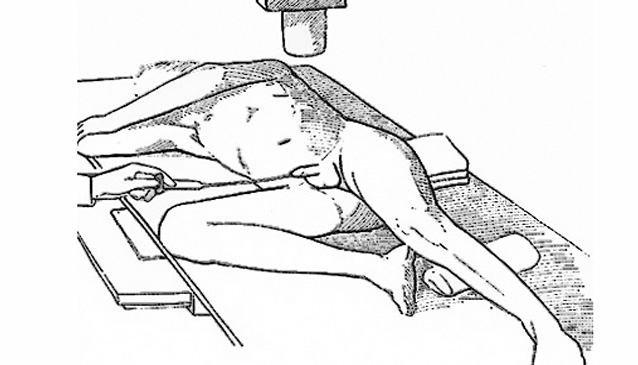

El procedimiento implica la inserción de una sonda de Foley en la «fosa navicular» que es el punto más amplio de la apertura de la uretra a nivel del glande masculino. A ese nivel se infla levemente el balón de la sonda con 1 a 2 ml de líquido. Ello es seguido por la lenta inyección de 30mL de contraste soluble en agua mientras se obtienen varias radiografías sencillas con la persona en posición oblicua al plano de la radiografía para poder observar la uretra en la imagen.2 El escape del contraste fuera de la uretra sugiere daño uretral (normalmente secundario a trauma pélvico) y es indicación para una intervención quirúrgica reparadora